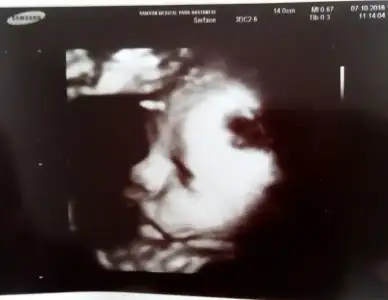

Kizlar bugun nst randevum vardii doktor ultrasonda da baktii tosuruk suratimi yine gormuss oldumm :KK46: hersey yolunda saglikli pasam cok sukur